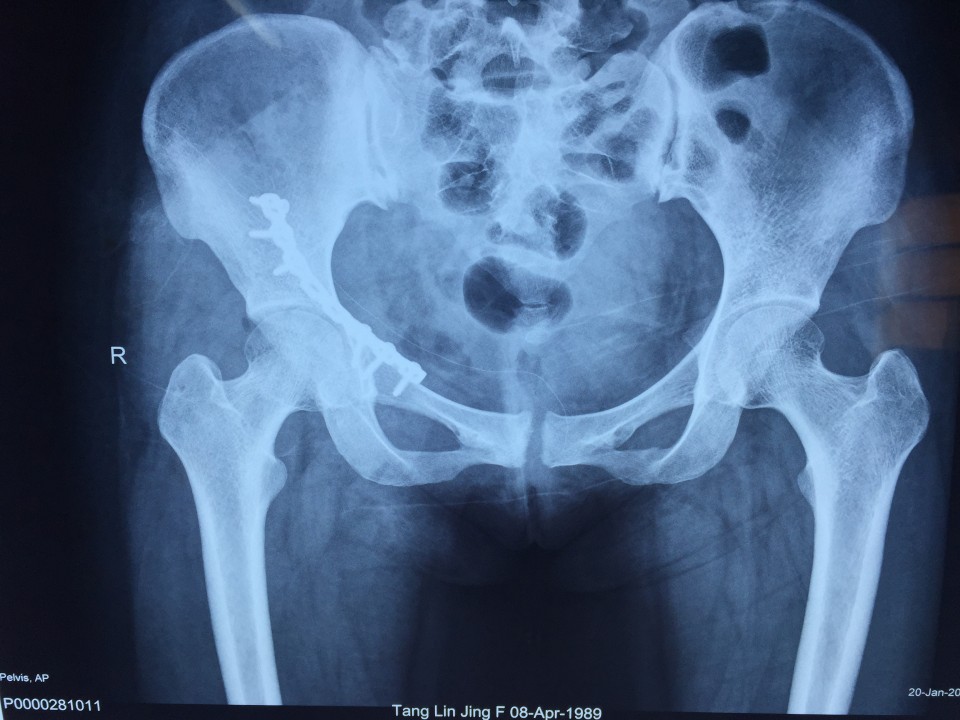

近日,我院创伤骨科七东利用改良Stoppa经腹白线旁入路成功治疗一例髋臼骨折患者。该患者女性,27岁,骨盆车祸伤。术前检查诊断为右侧髋臼骨折(AO分型为A3型)。该患者有剖宫产病史,腹部组织粘黏严重,手术难度较大。经过科室专家多次会诊,刘德宝主任制定详细手术方案,决定术中采用改良Stoppa入路,以减少手术创伤的影响。最终该手术顺利完成,历时一小时余,术中出血仅200ml,术后患者恢复良好。 采用改良Stoppa入路治疗髋臼骨折为安徽省首例,标志着我院创伤骨科进一步迈入创伤省内领先,国内先进的水平。

传统的对于髋臼前壁骨折的治疗方式主要为髂腹股沟入路,此入路内有重要的神经、血管经过,操作费时,术中可能导致股神经、血管及股外侧皮神经、精索或圆韧带的损伤。且骨折需通过3个窗口显露,骨折区域显露有限。针对髂腹股沟入路的缺点,我们使用改良Stoppa入路弥补了髂腹股沟入路的不足,它采用腹白线旁入路,推开腹膜内脏器,腹膜外达到真骨盆缘,一个窗口获得骨盆术野,可很好显露骨盆环。它有以下优点:此入路有宽阔的视野,并能直视骨盆缘,故可有效处理“死亡冠”,减少出血的发生;钢板塑形简单,钢板置入区域真骨盆内缘平坦,只需在一个平面预弯即可,并不需扭转钢板;可双侧骨盆缘复位固定,对于双侧耻骨上支及髋臼前柱骨折可轻易达到;术后病人康复快,因患者经下腹正中入路,并未损伤到髋部周围各层肌肉组织,故患侧肢体术后康复较快。据悉,此项技术在国内仅少数医院开展,在省内尚属首例。